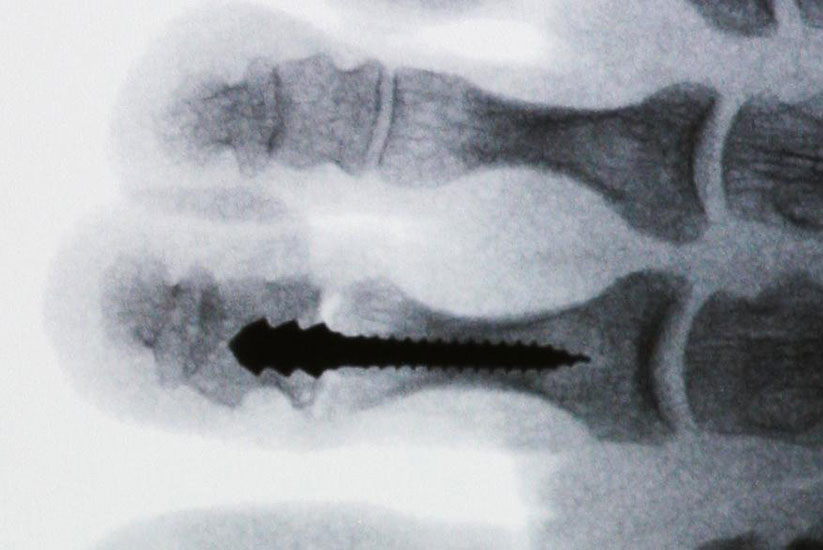

Ziel der PIP-Arthrodese ist die Aufhebung der Flexionsfehlstellung im PIP-Gelenk sowie die Erlangung einer ausreichenden mechanischen Stabilität um Rezidive bzw. Fehlstellungen zu vermeiden. Das Operationsprinzip der Korrektur basiert auf einer knöchernen Verkürzung im Bereich des PIP-Gelenkes um eine spannungslose Extension zu ermöglichen. Neben einer vollständigen Entknorpelung der Gelenkflächen wird eine postoperative Stabilisierung durchgeführt, um eine knöcherne Fusion zu erzielen. Die dazu am häufigsten verwendete Technik ist die Fixierung mittels intramedullärem Kirschner-(K-)Draht, der im Bereich der Zehenkuppe ausgeleitet und nach einigen Wochen entfernt wird. Alternative Fixationsverfahren sind die Verwendung von Mini-Schrauben oder resorbierbaren intramedullären Pins.

Eine relativ neue Entwicklung stellt die Verwendung spezieller intramedullärer Implantate dar. Mittlerweile sind eine Vielzahl unterschiedliche Systeme auf dem Markt. Ein wichtiges Unterscheidungsmerkmale ist die Art der Verankerung im Knochen. Dabei kann zwischen Systemen die eingeschraubt werden und Press-fit-Systemen, teilweise unter Verwendung von Formgedächtnislegierungen, unterschieden werden. Zudem wird zwischen einteiligen und zweiteiligen Systemen unterschieden. Bei zweiteiligen Systemen werden beide Komponenten getrennt implantiert und danach ineinander gesteckt.

PIP-Arthrodese unter Verwendung des Pro-Toe®VO-intramedullären Implantates

Die vorbereitenden Operationsschritte werden im Abschnitt „PIP-Arthrodese mit K-Draht-Fixierung“ in den Abbildungen 1.1 bis 1.7 beschrieben.